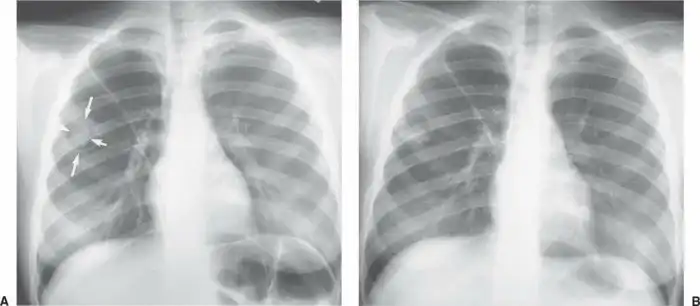

Рентгенограмма небольшой грибковой опухоли:

Женщина начинает готовиться к своим похоронам и искать место для операции, обзванивая платные раковые центры. Её навещают родные, близкие и друзья. Её поддерживают, и это здорово. Ей становится хуже с каждым днем. Хотя ничего, кроме КТ и рентгена, на рак не указывает. Её переводят в разные учреждения, пока медицинская комиссия вместе с врачом-диагностом не ставит под подозрение диагноз, основанный только на снимках. Посовещавшись в медицинских кругах, они начинают подозревать, что это может быть и не рак. Назначают новые анализы. В их числе анализ имунноглобулина Е к аспергиллезу. Полученный результат оказался настолько высоким, что был вне оценочной шкалы. У женщины обнаружили запущенный и разросшийся аллергический бронхолегочный аспергиллёз. Картина была настолько жуткой, что и КТ, и рентген в точности совпадали с характеристиками и внешним видом злокачественной опухоли, занимавшей почти всё легкое.

Рентгенограмма большой грибковой опухоли: